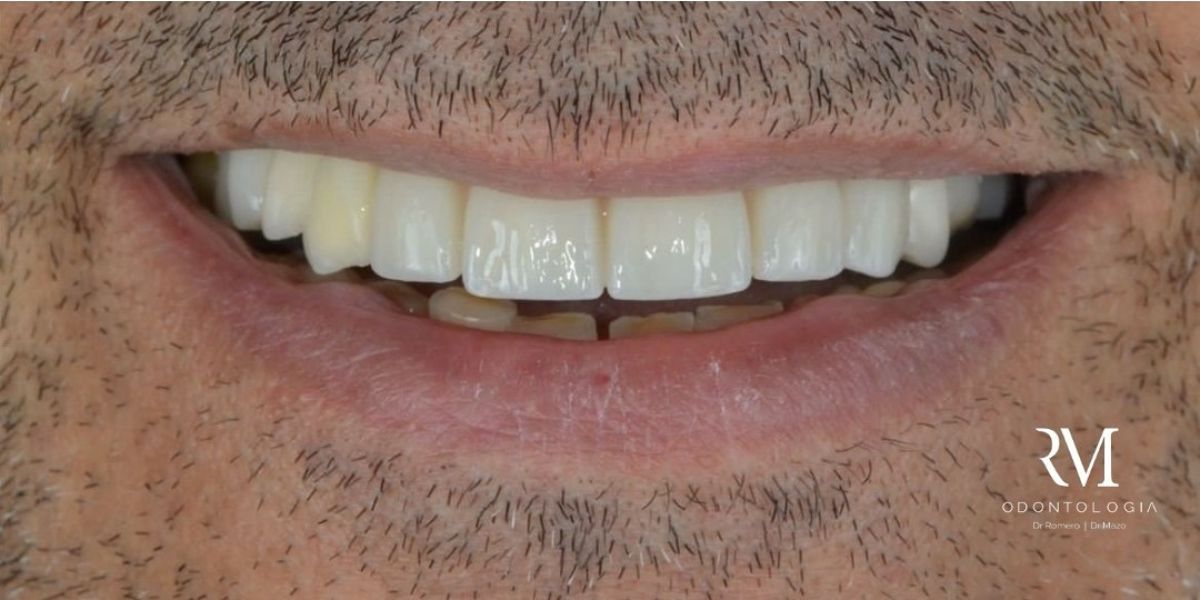

Smiles we’ve transformed through implant treatments

Every smile tells a story, and at RM Odontología, we have many to share. Here are a few real-life cases from our clinic.

Immediate load implants

Restore your smile in record time. In selected cases, we place both the implant and the provisional prosthesis on the same day, with no need to wait for months.